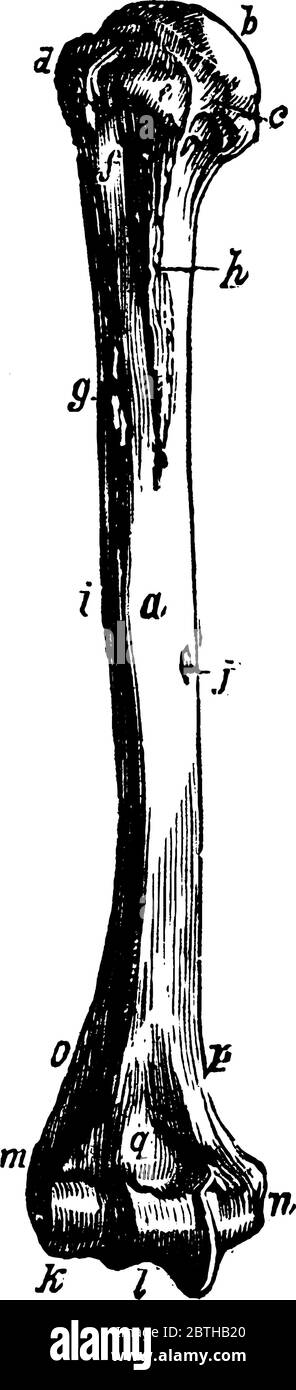

RF2BTGJYJ–Der Humerus ist ein langer Knochen des oberen Gliedes zwischen Ellenbogengelenk und Schulter, Vintage-Linie Zeichnung oder Gravur Illustration.

RF2BTHB20–Der Humerus ist ein langer Knochen des oberen Gliedes zwischen Ellenbogengelenk und Schulter, Vintage-Linie Zeichnung oder Gravur Illustration.